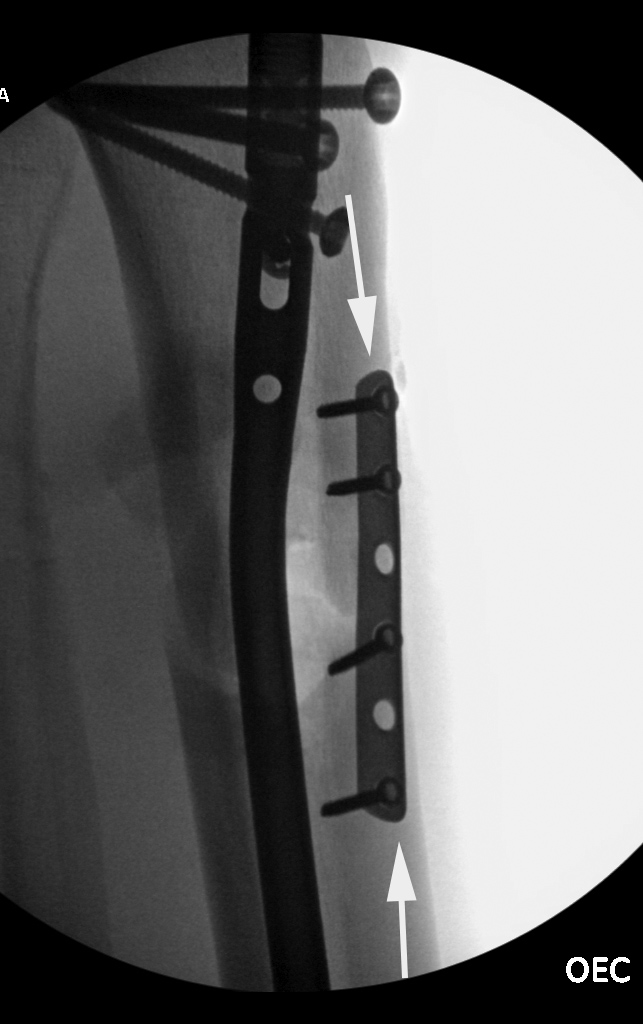

| Male patient with proximal tibia and fibula fractures treated by intramedullary nail and supplemental one-third tubular plate. Initial intraoperative fluoroscopic AP and lateral images (left two images) show the plate (arrow on lateral image). The patient ambulated against advice and was lost to follow-up. Two months later he again presented (right two images) to the clinic. There is now tibia fracture migration, and the proximal medial to lateral interlocking screw has backed out (AP view). The lateral view demonstrates fracture displacement with flexion deformity. The nail has troughed outside the proximal anterior tibia and is sitting within the soft tissues. The supplementary plate is broken, there is a broken interlocking screw, and abundant fracture callus is present. |